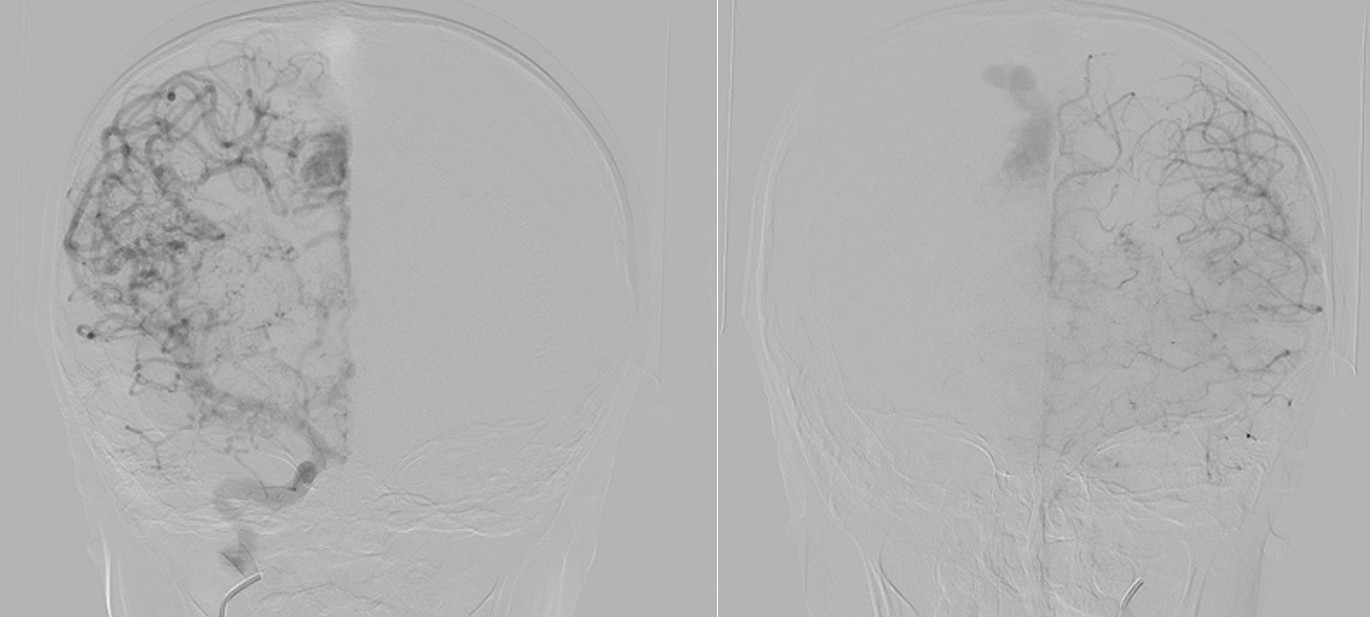

Digital subtraction angiography (DSA) confirmed the presence of two AVMs: one fed by distal branches of the right ACA and draining into the superior sagittal sinus, and another fed by MCA branches, draining into the internal cerebral vein. Capillary anastomoses were noted between the two AVMs. Selective bilateral internal carotid artery (ICA) injections revealed globally abnormal, tortuous arteriolar networks with delayed capillary filling, more pronounced on the right side (Figures 5, Figure 6, Figure 7). Based on these findings and the revised 2021 diagnostic criteria, the patient was diagnosed with MMD—characterized by stenosis of the intracranial ICA, narrowing at the terminal portion, and the development of abnormal collateral networks in the basal ganglia and periventricular white matter.4